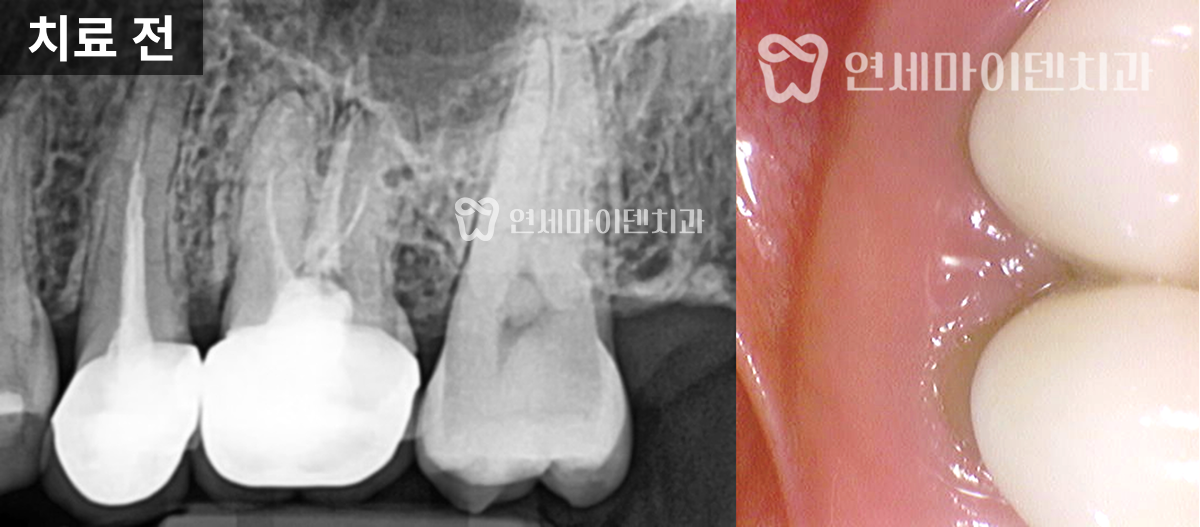

이 환자분은 '예전에 신경치료를 받았던 왼쪽 위 어금니쪽이 시린 증상이 있고 아프다'며 내원하셨는데요.

두 개의 치아 모두 불편함이 있었고, 모두 치료를 받은 지 꽤 되었으며, 염증이 있는 상태였습니다.

정확한 진단을 위해 환자분의 덴탈 히스토리, '언제 치료를 받으신 건지', '언제부터 통증이 있었는지'를 물어보고, '악화 요인이 무엇인지'를 정확히 파악하려 했습니다. 엑스레이나 CT도 중요하지만, 이런 덴탈 히스토리까지 진단에 포함되어야 환자분의 불편함을 정확하게 해소할 수 있습니다.

살펴보니 과거에 받으셨던 신경치료의 퀄리티가 아쉬운 부분이 있었습니다.

신경관뿌리까지 치료가 되어있지 않고, 중간에 갭이 보였습니다.